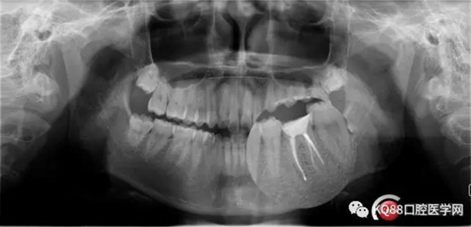

X-ray:36根尖云霧狀低密度影,根分叉未見異常。

診斷:36慢性增生性牙髓炎。

1.png

2.png